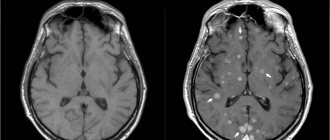

Что показывает электроэнцефалография головного мозга?

Электроэнцефалограмма, как метод исследования, исторически использовался во многих клинических ситуациях. По разнице получаемых сигналов, по превалирующим ритмам мозга определяли очаговые образования мозга. Также некоторые невротические состояния, ДЦП и другие пороки развития имеют свои особенности, проявляющиеся на ЭЭГ. Однако в современной медицине у неврологии осталась малая ниша показаний. ЭЭГ используют для диагностики эпилепсии, также, гораздо реже, ЭЭГ показана для диагностики редких заболеваний, например, спонгиоморфных энцефалопатий (в частности, болезни Крейтцфельдта-Якоба). Также исследование может служить методом оценки эффективности проводимой противосудорожной терапии.

ЭЭГ показывает организованность и превалирование ритмов мозга, позволяет обнаруживать патологические ритмы и феномены. Наличие патологических элементов, разница ритмов и их дезорганизованность по различным отведениям, может указывать на дисфункцию различных отделов мозга. Также эпилептиформные феномены позволяют диагностировать эпилепсию. Абсолютно достоверным считается такой диагноз, при котором во время записи исследования был зафиксирован приступ эпилепсии, имеющий свои характерные особенности на пленке.